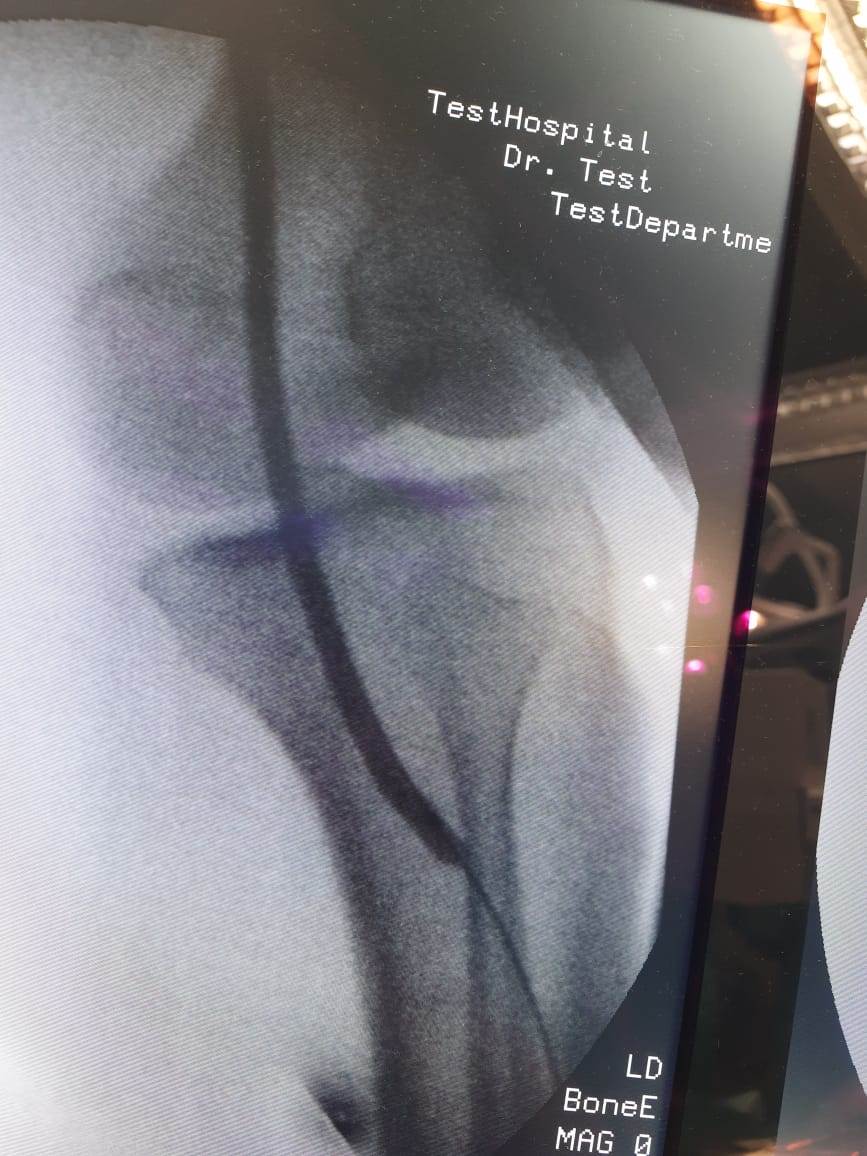

وأوضحت الهيئة برئاسة الدكتور أحمد السبكى رئيس مجلس الإدارة، أنه فور حضور المريضة محولة من وحدة صحة القرايا إلى مستشفى حورس التخصصي، بنظام الإحالة الطبية المعمول به في نظام التأمين الصحي الشامل الجديد، تم إجراء الفحوصات الطبية اللازمة لها، وتبين أنها تعاني من قصور حرج بالدورة الدموية بالطرف السفلي الأيسر وغرغرينا بالقدم نتيجة انسداد الشريان الفخذي والمأبضي الأيسر؛ وعليه تم عمل توسيع للشرايين باستخدام البالونات الموسعة واستعادة الدورة الدموية حتى القدم وإنقاذ ساق المريضة من البتر، وهي الآن بحالة صحية جيدة وحالتها مستقرة.